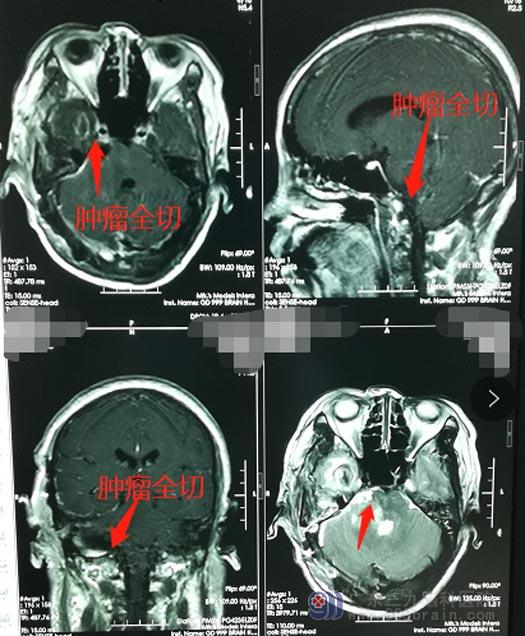

充分地术前准备后,李阿姨接受了“右侧桥小脑角区脑膜瘤切除术”,鲁明带领手术团队经过10个小时的努力,在显微镜下将乒乓球大小的肿瘤完整切除,手术过程顺利。

术后,李阿姨兴奋地告诉周围的人:“能听见了,终于能听见了!”